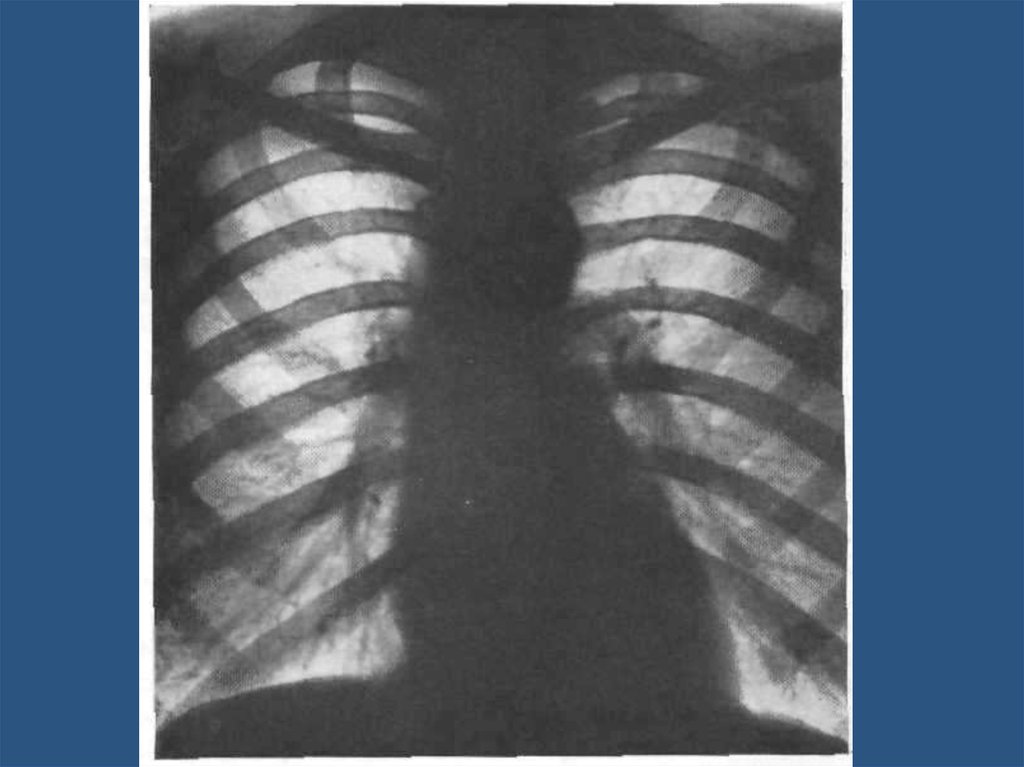

Рак правого бронха в прямой и боковой

проекции